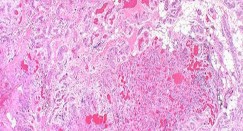

Question 17

A 35-year-old female is diagnosed with a locally aggressive giant cell tumor of the distal radius. Preoperative administration of Denosumab is planned to facilitate downstaging and joint-salvage surgery. What is the exact mechanism of action of Denosumab in this context?

Explanation

Denosumab is a fully human monoclonal antibody that specifically binds to RANKL (Receptor Activator of Nuclear factor Kappa-B Ligand). By binding to RANKL, it prevents it from interacting with the RANK receptor on the surface of osteoclasts and osteoclast precursors. In Giant Cell Tumor of bone, the neoplastic mononuclear stromal cells express high levels of RANKL, which aggressively recruits and activates the reactive multinucleated giant cells (osteoclasts) that cause bone destruction.